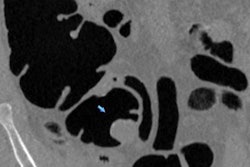

Unlike in the case of lung cancer, payment for colorectal cancer screening with CT colonography is not covered by the U.S. Centers for Medicare and Medicaid Services. Learn why a group from the University of Wisconsin believes CT colonography reimbursement may be warranted for seniors in the Medicare program.